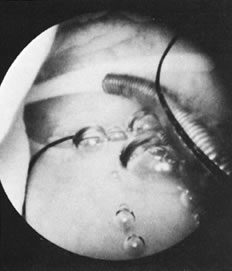

We find hysteroscopy to be of great value in the management of patients with lost IUDs (Figs. 22, 23, 24, and 25). In our experience with 91 hysteroscopic examinations of patients wearing IUDs that they could not feel or that a clinician could not see on examination, successful location of the lost IUD confirmed the validity, safety, and effectiveness of the procedure, as well as its advantage in terms of avoiding unnecessary radiographs and blind manipulations (Tables 3 and 4).26,27

Fig. 22. A fragmented Dalkon shield IUD partially embedded in the uterine wall.

Fig. 23. Copper-7 IUD within the uterine cavity; its filament is in the uterine fundus.